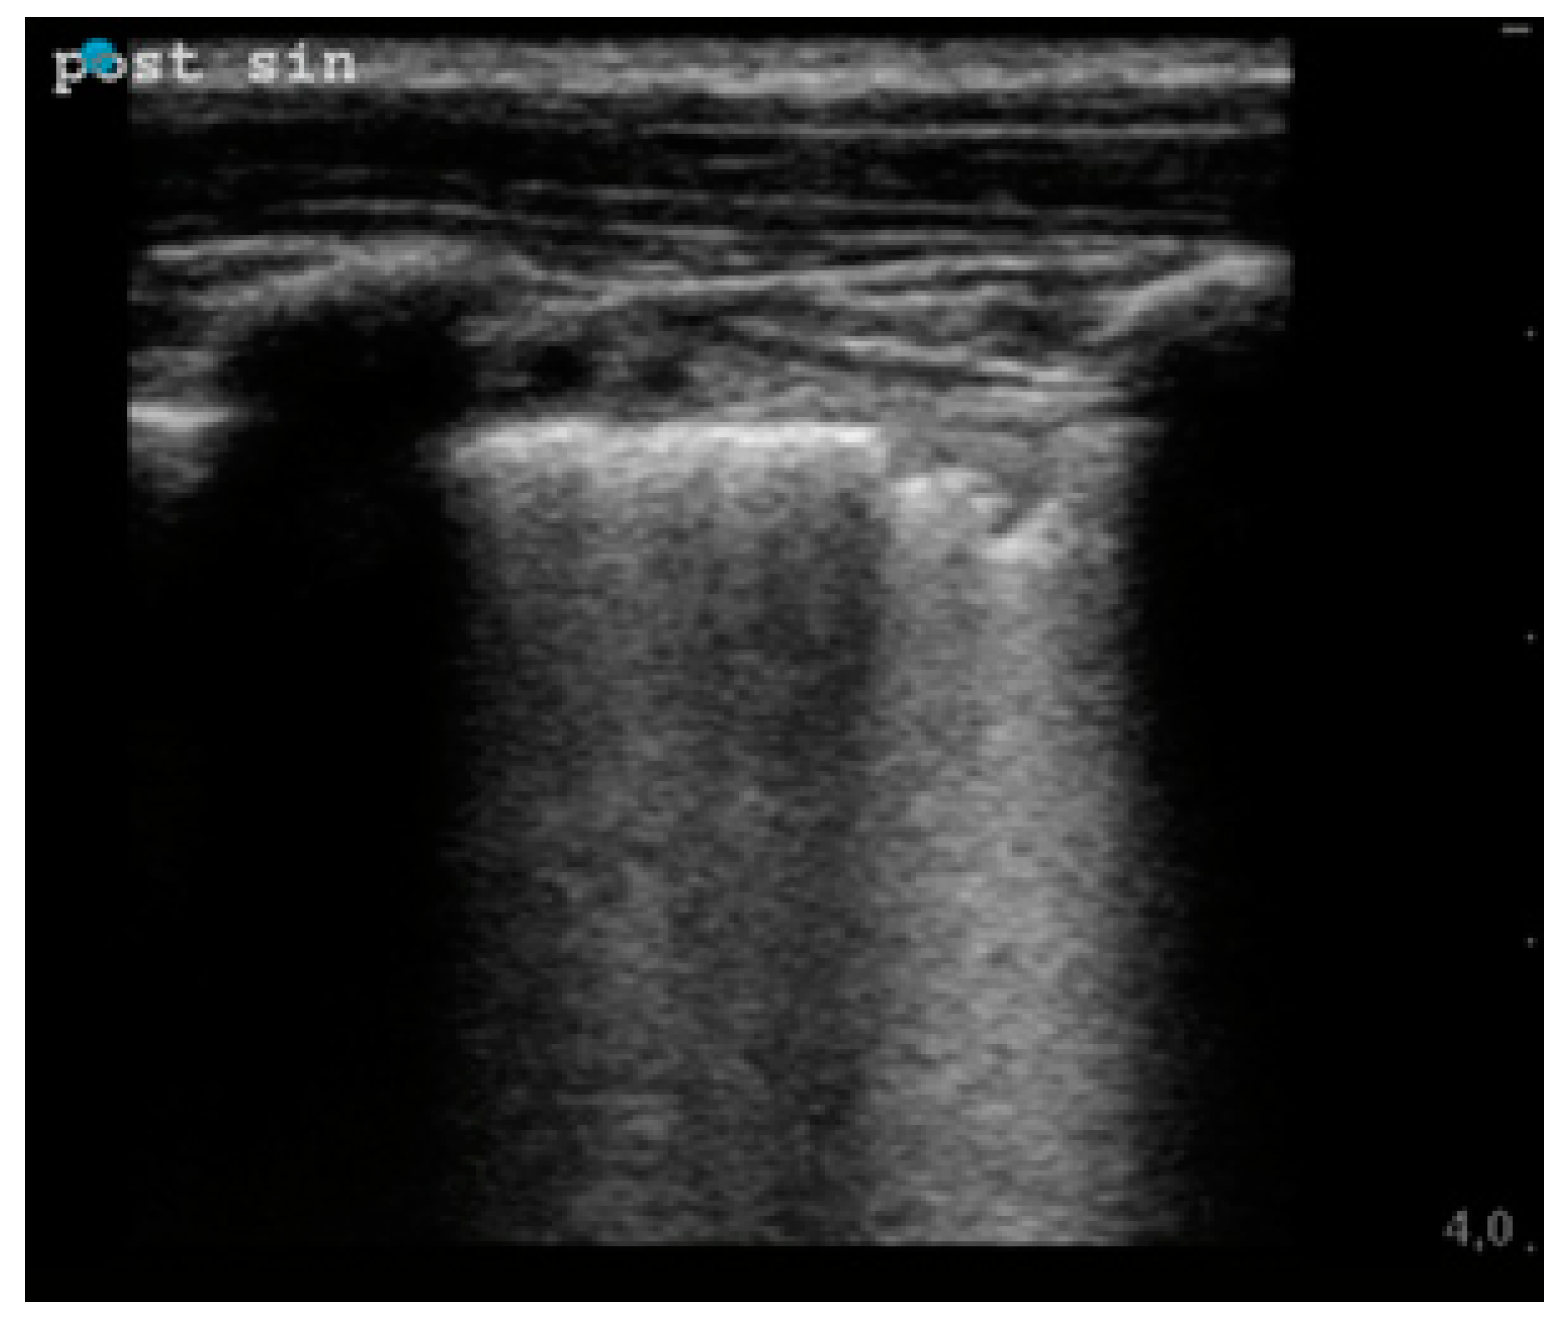

| Sub-pleural consolidation, n (%) | 2 (7.14) | 8 (28.57) | 0.04 |

| Irregular pleural line, n (%) | 17 (60.71) | 24 (85.71) | 0.035 |